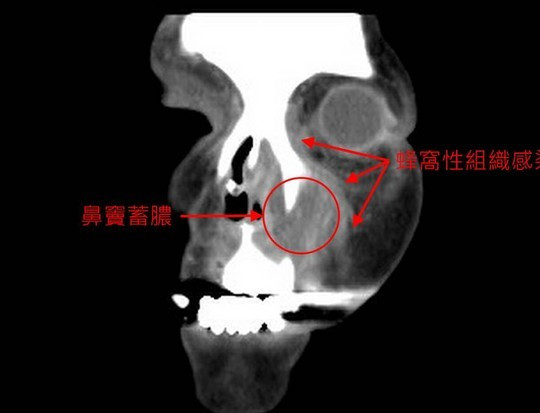

来到沈阳四院眼科就诊时,小陈的左眼已经睁不开了,急诊眼眶CT显示:眶内积气、颅内积气伴有炎症,这是急性鼻窦炎引发的眼眶周围蜂窝组织炎,如不及时治疗将有失明的危险!

急转耳鼻咽喉科!徐振明主任及鼻颅底专业组訾龙医生紧急为小陈实施了手术,鼻内镜下清除了鼻窦腔感染源,成功控制蜂窝组织炎。术后,小陈左眼睛已全部睁开,视力恢复,头痛减轻,现正逐步恢复中。

经与小陈沟通,医生了解到,此次病情恶化多与其不正确的擤鼻涕方式有关。四院耳鼻喉科訾龙医生介绍:两侧鼻孔用力擤鼻涕,就像吹气球一样,会把鼻腔、鼻窦里的脓性分泌物加压挤到眼眶和颅内或中耳腔,可继发视神经炎、脑膜炎、中耳炎等,这在小儿患者中比较多见。